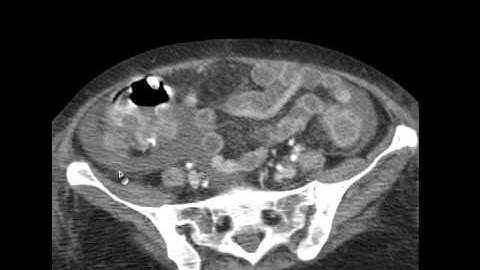

C. difficil Pseudomembranous colitis - axial CT